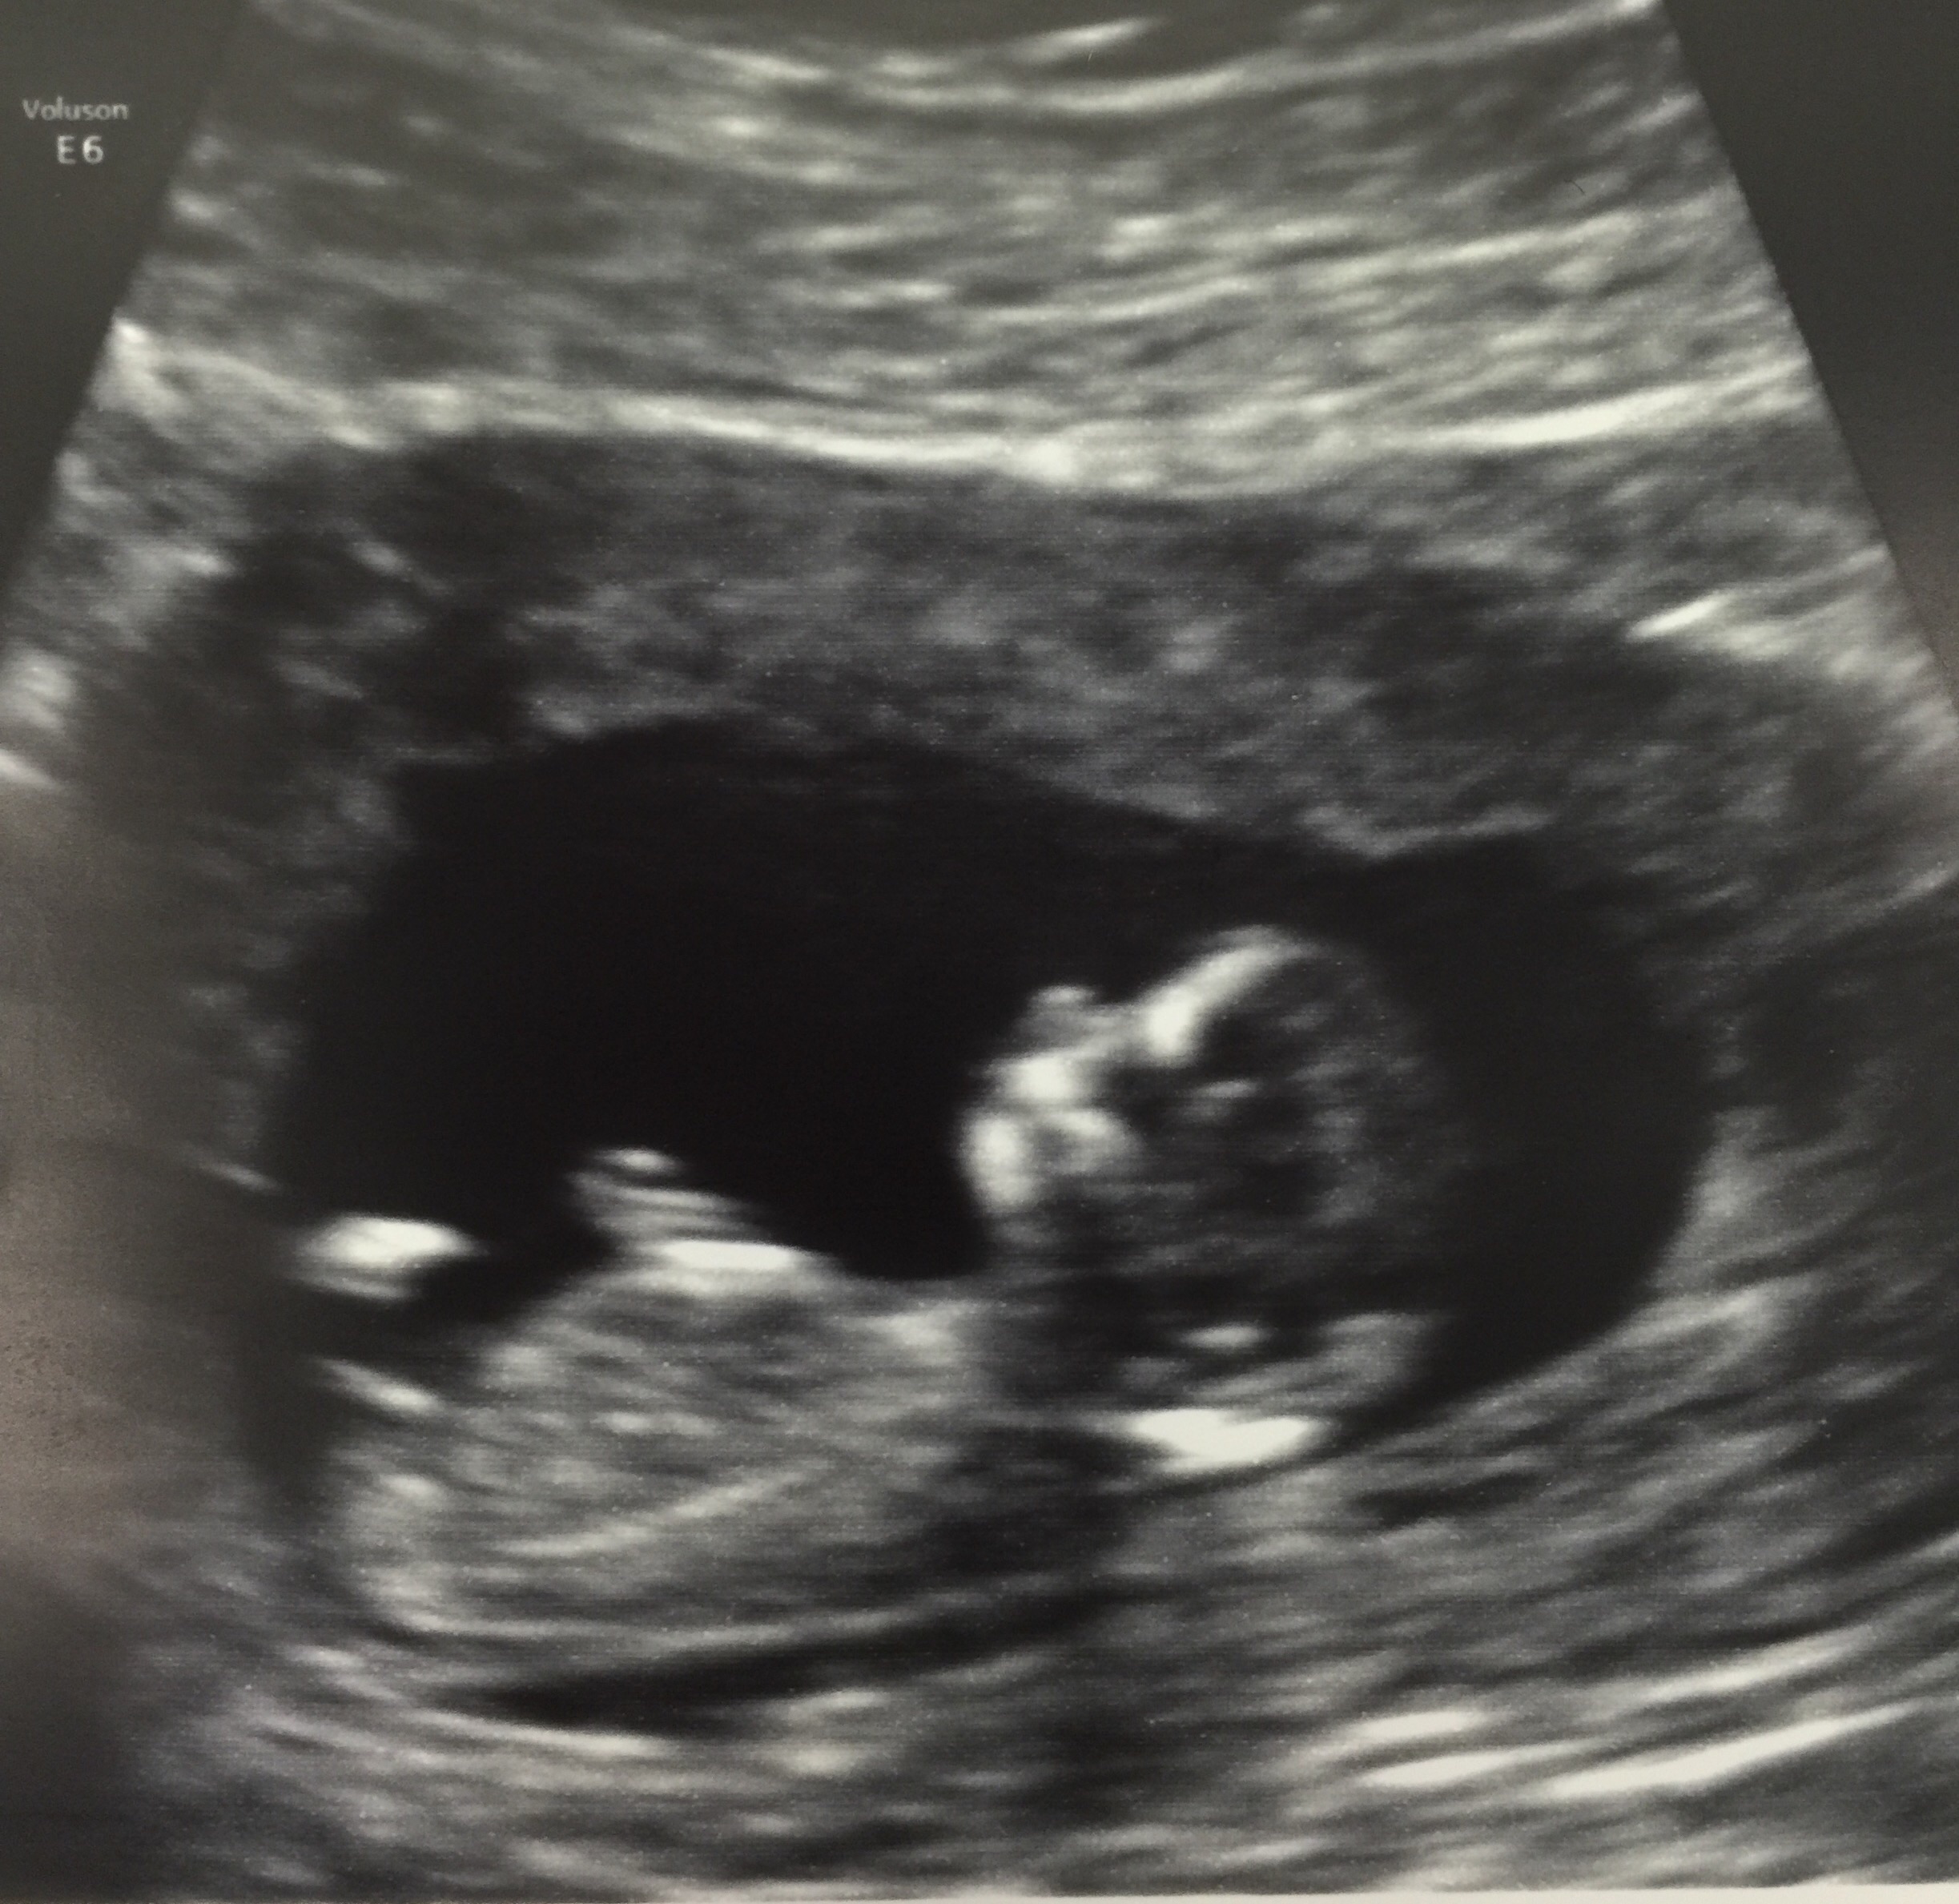

Had our first ultrasound yesterday! Found out I'm 11w2d which means I'm teetering between November/December. My due date as it stands is November 24th so right around thanksgiving It was just so surreal seeing the baby there with my DH. We were both just so happy to see a little baby there... it waved its arms a bit which was just so adorable.

Didn't catch what the heartrate was, but we definitely saw its little heart flickering Just so freaking amazing